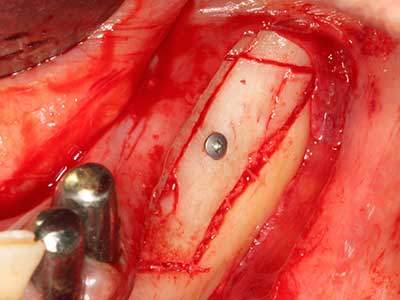

Piezo surgery has additional advantages when harvesting bone blocks. In addition to the high precision with osteotomy described above, the use of the thin saw tips specifically minimizes loss of material. Greater loss of material during harvesting can be expected with the thicker instrument tips, particularly when using Lindemann drills (Lakshmiganthan, Gokulanathan et al. 2012). The basal separation, which is necessary particularly for retromolar block transplants, is simplified by specially designed rectangular saws, with the result that piezo surgery is viewed as a precise, simple and safe procedure for harvesting retromolar bone blocks (Happe 2007) (Fig. 1-12).

Indication: Bone splitting